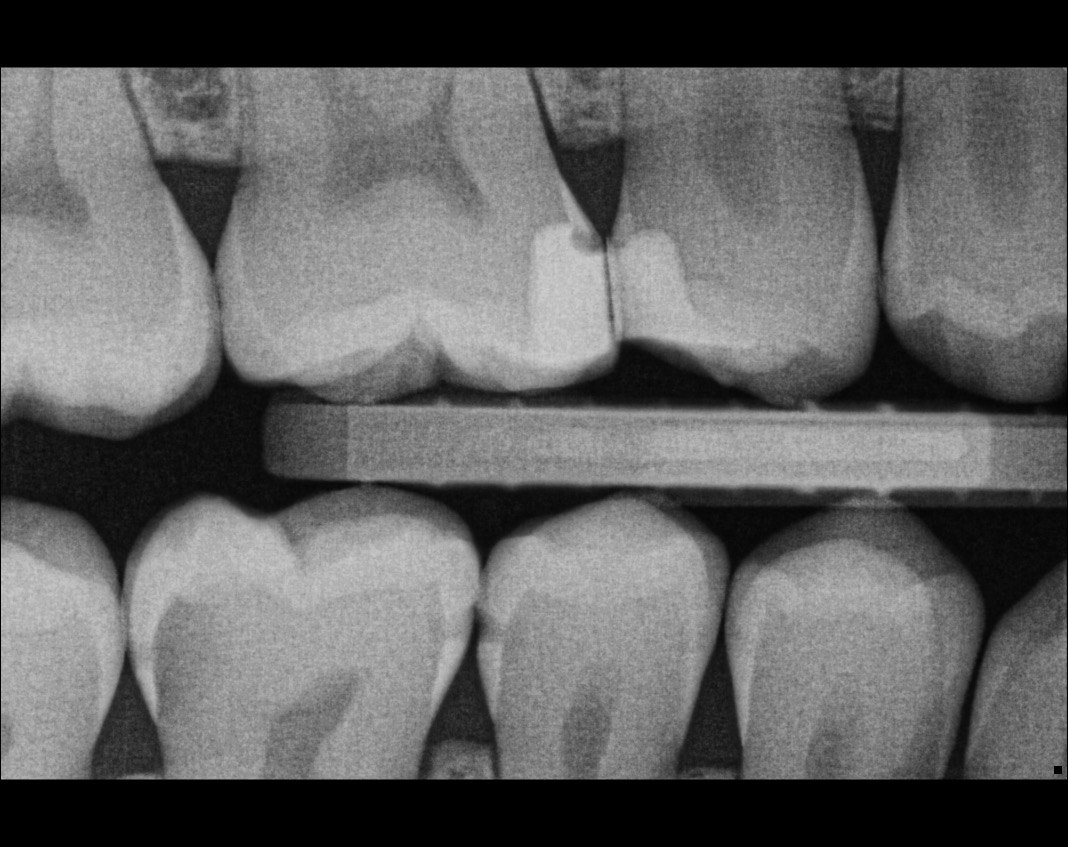

Question 1: What is the condition of the mesial surface of the tooth # 2.6?

Question 2. What is the condition of the mesial of the tooth # 2.7?

Question 3. What is the condition of the distal surface of the tooth # 2.7 and mesial surface of the tooth # 2.8 respectively?